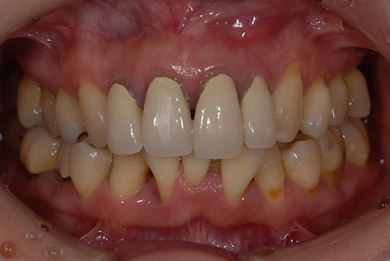

| 性別/年齢 | 女性 / 40歳 | ||||||||||||||||||||||||||||||||

| 主訴 | 前歯のつけ根の黒い部分を見えないようにしたい。 | ||||||||||||||||||||||||||||||||

| 治療方針 | 上顎前歯をセラミック治療にて審美的回復を行う。 | ||||||||||||||||||||||||||||||||

| 治療内容 | オールセラミッククラウン4本(セラミック用土台4本) | ||||||||||||||||||||||||||||||||